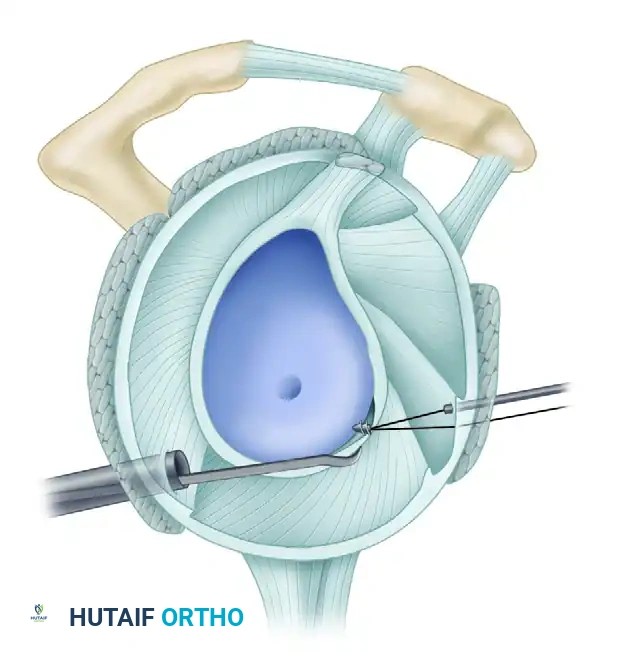

5. Recreating the Anterior Bumper

Proceed superiorly, placing the second and third double-loaded anchors. Firmly secure the sutures, compressing the capsuloligamentous complex to the abraded bone surface. This "loop and knot fixation" rolls the tissue up onto the glenoid face, recreating a robust anterior soft-tissue bumper.

D, Knots tied re-creating soft tissue bumper.

6. Rotator Interval Closure

If the patient exhibits baseline hyperlaxity and a significant sulcus sign that persists after the Bankart repair, a rotator interval closure is mandatory to address the superior glenohumeral ligament (SGHL) and coracohumeral ligament (CHL) laxity.

- Withdraw the anterior central cannula just outside the capsule.

- Pass a crescent Spectrum needle through the IGHL, several millimeters into the ligament, and into the joint.

- Maintain one limb outside the capsule. Retrieve the intra-articular limb using a penetrator device at the level of the SGHL.

- Tie the sutures extracapsularly using an SMC knot. Generally, two sutures are sufficient. The slight loss of external rotation is a necessary trade-off for the added inferior stability.

Completed Bankart repair with three anchors and capsule plicated inferiorly. Rotator interval is closed.